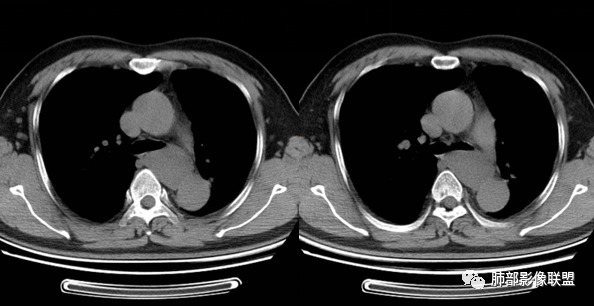

男性,43岁,体检发现后纵隔占位,边缘光整,CT示密度均匀,周围组织受压移位,无钙化囊变及脂肪组织,增强未见明显强化。MRI:T1示肿块信号较肌肉高,T2不均匀高信号。考虑为良性病变,第一是神经节细胞瘤,其次是支气管源性囊肿。

定位,后纵隔囊性占位,边界清楚,内部密度均匀,张力高,囊壁均匀,周围结构受压,增强后无强化。MRI:长T2信号。考虑良性囊性病变,支气管囊肿、淋巴管囊肿。

气管、左主支气管后方,食道左侧囊性占位,壁薄且均匀、光滑。气管及左主支气管受压凹陷、变形。

食道也受压变形、移位。

(2)囊液密度均匀,根据性质的不同而呈不同密度,可为近似水样密度,也可为较高密度,因为囊壁分泌粘液,所以囊内密度一般高于其他纵隔囊肿,CT值多大于20HU甚至超过60HU;

(3)若囊肿内密度较高时与实性肿块鉴别较为困难,增强扫描囊液无强化为鉴别要点;但是囊壁因为含有平滑肌成份,所以可能环形强化;如果病灶合并感染,病灶壁也会明显强化。